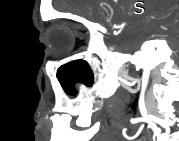

Золотым стандартом в диагностике патологических процессов пазух носа является мультиспиральная компьютерная томография. Это быстрый безболезненный и неинвазивный (то есть без вмешательства в организм) способ исследования состояния синусов. Метод основан на проникающей способности ионизирующего излучения и получения изображений органов и тканей организма за счет разной степени поглощения ими рентгеновских лучей.

Рентгеновские лучи лучше всего поглощаются костной тканью, поэтому кости хорошо видны на снимках КТ. Чтобы улучшить визуализацию мягких тканей и особенно патологических образований (в том числе полипов или опухолей), применяется внутривенное болюсное контрастирование. Для этого пациенту в вену вводится йодсодержащее контрастное вещество, которое улучшает видимость патологического очага на фоне здоровых тканей. С помощью методики контрастирования удается выявлять опухоли минимальных размеров, что повышает шансы пациента на успешное лечение и выздоровление.

Современные компьютерные томографы позволяют получать подробные изображения исследуемой области и при этом минимизировать дозу облучения для пациента. Наши медицинские центры оборудованы новейшими мультиспиральными компьютерными томографами экспертного класса TOSHIBA AQUILION в различных модификациях.

Аппараты имеют увеличенное количество детекторов, благодаря чему за один оборот кольца гентри (кольцеобразной рамы томографа) производится от 64 до 128 послойных снимков с толщиной срезов от 0,5 мм. Сверхчувствительные детекторы обеспечивают максимальное качество изображений, при этом время исследования сокращается и пациент получает уменьшенную дозу облучения.

На основе полученных данных цифровые приложения томографов создают трехмерные реконструкции пазух носа, что позволяет оценить пространственное взаимоотношение анатомических структур и помогает в диагностике патологии околоносовых пазух.

Мультиспиральная компьютерная томография дает информацию о состоянии полости носа, носовой перегородки, степени воздушности околоносовых пазух, путей дренирования синусов, состоянии слезных каналов. Сканирование позволяет оценить толщину слизистой, наличие патологического содержимого в просвете пазух (уровня «жидкости»), выявить опухолевые образования. С помощью КТ можно провести точную диагностику травматических повреждений костей лицевого черепа, определить локализацию инородных тел, попавших в полости синусов.

С помощью объемной реконструкции можно перед оперативным вмешательством увидеть особенности анатомии ЛОР-органов, определить точное расположение патологического очага по отношению к окружающим тканям. Компьютерная томография помогает в диагностике аномалий развития придаточных пазух носа, слезоотводящих каналов.

Кроме того, контрастное вещество ярко контрастирует патологические очаги на фоне здоровых тканей, в результате чего удается выявить опухоли минимальных размеров, отличить доброкачественные опухоли от злокачественных, диагностировать онкологические заболевания на ранней стадии. С помощью методики можно определить точные размеры опухоли, степень прорастания в соседние ткани, оценить состояние регионарных лимфоузлов.